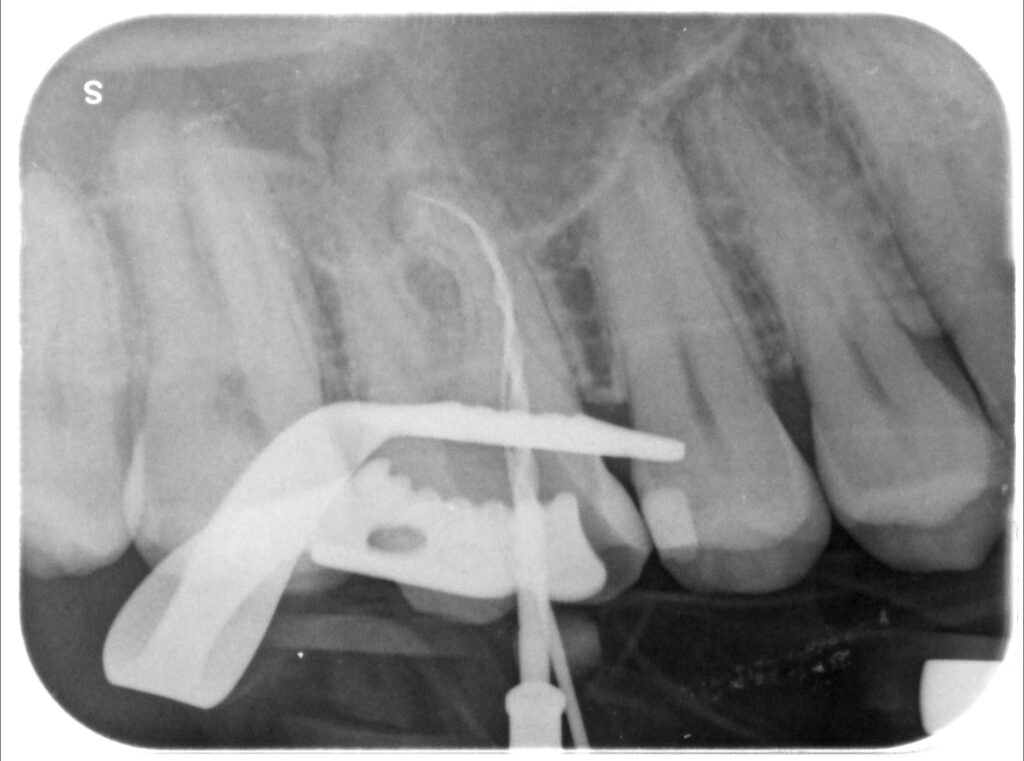

Caso clinico – trattamento ortogrado 1° molare superiore con lesione